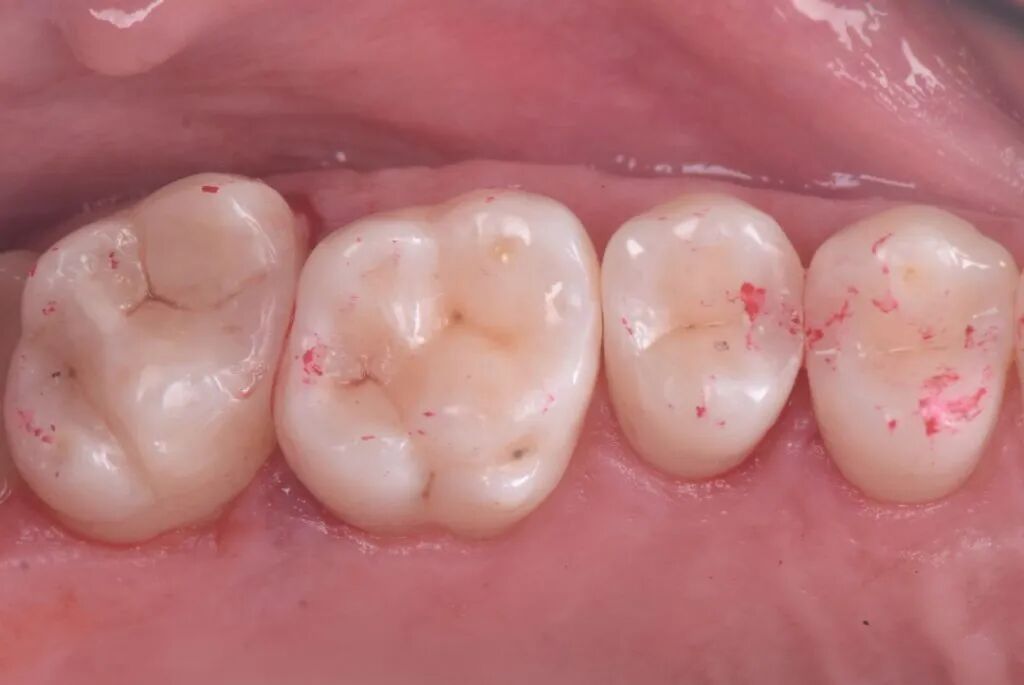

图11. 光固化垫底材料置于27窝洞最深处。

图12. 光固化20秒。

图13. 垫底后准备充填修复。